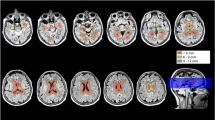

Follow-up pairwise comparisons revealed that compared to their respective control groups without dementia, both DS+ and AD had a highly significant reduction in the volume of the hippocampus, and AD (but not DS+) had a highly significant reduction in the volume of the temporal lobe and a highly significant increase in the volume of the lateral ventricles. DS+ had a highly significant reduction in the volume of the hippocampus compared to DS-. Compared to the DS healthy control group (the younger healthy control group), both DS+ and DS- had a highly significant reduction in WBV (Figure 1). The hippocampal and temporal lobe volume reductions in AD and DS+ were disproportionately greater than the WBV reduction.

There was a significant main effect of group for the hippocampus, temporal lobes and the lateral ventricles. There was a significant main effect of gender for the temporal lobe. Follow-up pairwise comparisons revealed that compared to their respective control groups without dementia, both DS+ and AD had a highly significant reduction in the volume of the hippocampus (Figure 2), and AD (but not DS+) had a highly significant reduction in the volume of the temporal lobe (Figure 3) and a highly significant increase in the volume of the lateral ventricles (Figure 4). DS+ had a highly significant reduction in the volume of the hippocampus compared to DS-.

Hippocampal volume corrected for total intracranial volume (TIV) (corrected as a ratio of the hippocampal volume to TIV). Comparison of people with Alzheimer’s disease (AD) and people with Down’s syndrome with dementia (DS+). HC, healthy controls; DS-, people with Down’s syndrome without dementia. *P <0.0001.

Temporal lobe volume corrected for total intracranial volume (TIV) (corrected as a ratio of the temporal lobe volume to TIV). Comparison of people with Alzheimer’s disease (AD) and people with Down’s syndrome with dementia (DS+). HC, healthy controls; DS-, people with Down’s syndrome without dementia. *P <0.0001.

Lateral ventricle volume corrected for total intracranial volume (TIV) (corrected as a ratio of the lateral ventricle volume to TIV). Comparison of people with Alzheimer’s disease (AD) and people with Down’s syndrome with dementia (DS+). HC, healthy controls; DS-, people with Down’s syndrome without dementia. *P <0.0001.